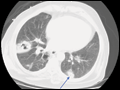

| Figure e34-31 CT scan of ARDS demonstrates "ground-glass" opacities with more consolidated areas in the dependent lung zones. | |